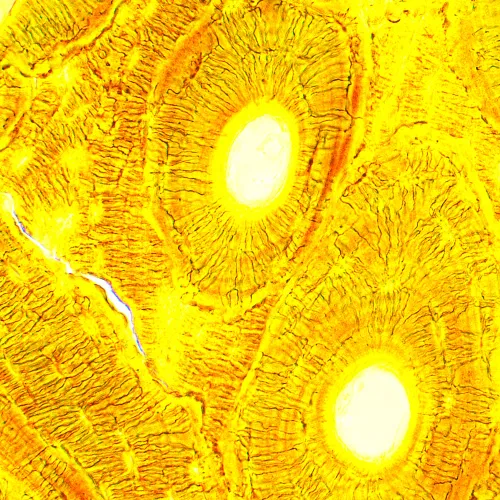

Тринокулярный биологический микроскоп MAGUS Bio 250T с отдельным каналом визуализации для установки цифровой камеры – отличный выбор для лаборатории, если планируются не только непосредственные исследования образцов, но и их фото- и видеофиксация. В микроскопе используются скорректированные на бесконечность планахроматические объективы и галогенный осветитель проходящего света, что позволяет с отличной детализацией наблюдать прозрачные и полупрозрачные образцы. Исследования проводятся в светлом поле, возможна установка дополнительных аксессуаров для работы в темном поле, поляризованном свете и с использованием фазового контраста.

Источником света выступает галогенная лампа мощностью 30 Вт. Теплый спектр освещения позволяет вести длительные наблюдения без перенапряжения зрения, а высокая яркость излучаемого света обеспечивает получение информативной картинки вне зависимости от используемого объектива и метода исследования. Яркость подсветки регулируется. Для питания используется сеть переменного тока.